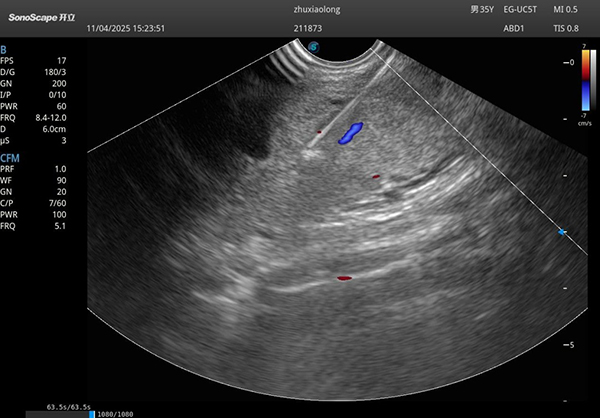

很快,肿物清晰地出现在屏幕上。我接上穿刺针,开启彩色多普勒,反复确认路径上没有血管。深吸一口气,稳、准、狠——针尖缓缓穿过食管壁,直抵病灶。我在肿物内部来回抽吸,心里默默计数:76、77、78……直到第80次,才满意收手。当一条条红白相间的组织如“小蚯蚓”般从针芯挤出时,我悬着的心终于放下大半——标本量足、质量好,病理有望明确!

穿刺针进入肿物内部穿刺图片